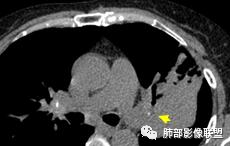

整个上叶尖后段阻塞性肺不张的表现,从强化来看没有异常结节状或肿块样强化,肿块内部点状钙化、纵隔多发小淋巴结、下叶背段有树芽征,整体来看支持肺结核,让人不放心的是最后一幅冠状位重建的图像尖后段支气管堵了,而且有轻度的隆起,所以很难除外粘液表皮样癌(女性,鳞癌可能性小),如果是我写报告肯定会建议纤支镜检查

考虑结核伴混合感染。中青年女性,持续低热、不正规抗感染症状加重。左上肺低密度肿块,左上固有段支气管未显影(结核侵蚀干酪样坏死),左上舌段支气管通畅但增厚变形。左下肺树芽征新发支气管播散。鉴别:粘液腺癌

左上叶实变不张,膨胀生长,上叶开口阻塞?,病灶内支气管扩张,明显延迟强化,内见低密度灶及点状钙化,周边见小叶间隔增厚丶结节,右斜裂结节

左肺病变支气管有狭窄后扩张,有部分钙化,符合结核,但叶间裂有膨隆,支气管有受压变窄表现,部分病灶内有血管,不能排除腺癌的可能,所以考虑肺结核合并腺癌可能

上叶支气管堵塞处稍萎缩、凹陷,附近壁增厚,内可见小点状钙化

树芽征、小叶间隔增厚,淋巴结, 内部血管走形自然

分析:支气管粘液栓、支气管堵塞处萎缩、钙化,支气管通畅处部分扩张,树芽征——提示结核。